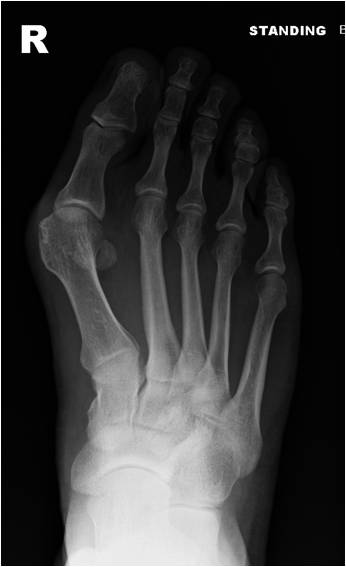

Symptoms include pain in the bump area with or without shoes and occasionally associated discomfort in the ball of the foot (metatarsalgia) and/or lesser toe deformities (Fig 2) such as a hammertoe from direct pressure of the big toe. The diagnosis is confirmed by clinical assessment and x-rays (Fig 3).

Several surgical techniques are available and Mr Weitzel will advise the patient of the most appropriate for her/his individual problem. This will often include a form of osteotomy (cutting and realigning of bone Fig 4) which is then fixed with internal implants such as screws and/or staples.